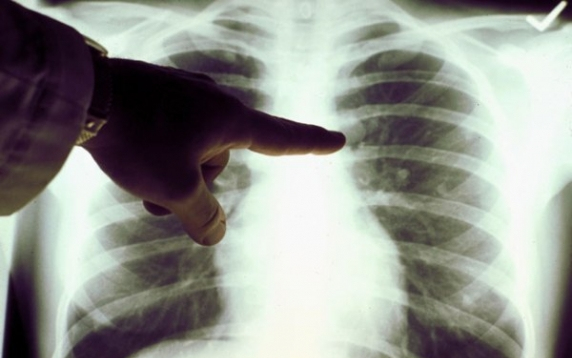

Mégsem állati eredetű a TBC

A tuberkolózis eredete hetvenezer évvel ezelőtti vadászó-gyűjtögető életmódot folytató afrikaiakhoz köthető – állapította meg egy tanulmány, amelyről a BBC számol be. A kutatás ellentmond annak az általános meggyőződésnek, hogy a tbc tízezer évvel ezelőtt, állatokról terjedt át emberre.

Korábbi tanulmányok azt találták, hogy a tbc tízezer évvel ezelőtt alakult ki Afrikában a neolitikum demográfiai átalakulása során, amikor emberek lepték el a kontinenst és a mezőgazdaság lett a meghatározó tevékenység.

A kutatás keretében a szakemberek 259 tbc törzs földrajzi és genetikai adatait gyűjtötték össze, s megerősítették az a hipotézist, hogy a tbc eredetileg emberekből indult ki, ráadásul hatvanezer évvel korábbról származik, mint azt eredetileg gondolták.

Amikor az emberi populáció elkezdett terjeszkedni, a tbc is aktívvá vált és képes volt a szaporodásra. A kutatás következő fázisában genetikai információk felhasználásával szeretnék megállapítani, hogy mi a folyamata a tbc aktiválásának, illetve inaktiválásának.

A tbc még mindig globális veszély, ami 2011-ben 1,4 millió ember halálát okozta.